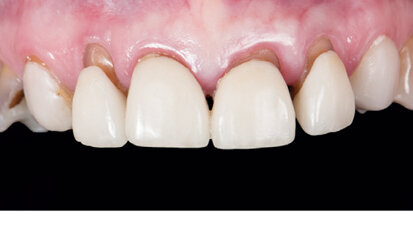

Nový úsměv za jeden den

Čt. 28. května 2020